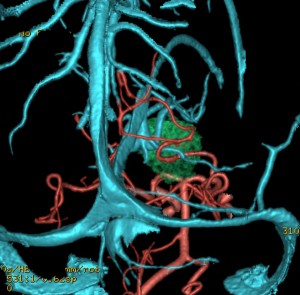

CTです

左のCTでは低密度の松果体腫瘍とまばらな石灰化がみられます。右の造影CTでは,腫瘍のごく一部が増強されます。 この時点で,低吸収で石灰化があるので類皮のう胞 dermoid cystを強く疑います。dermoid cystを主体とする混合性胚細胞腫瘍 mixed germ cell tumorも候補です。あるとすれば,germinomaかteratomaです。